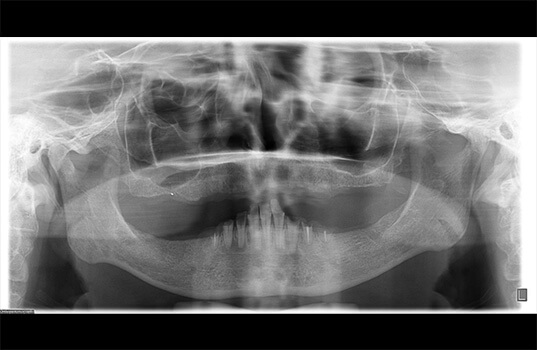

A Radiografia Panorâmica é uma radiografia de boca que fornece uma visão ampla dos dentes, mandíbula e maxila. É usada na odontologia para ajudar a identificar problemas dentários, como cáries, infecções, fraturas e outros problemas ósseos. Além disso, a Radiografia Panorâmica também pode ser usada para planejar tratamentos dentários, como a colocação de próteses e implantes dentários, como também para avaliar o desenvolvimento de tratamentos já realizados.

Na Radiografia Panorâmica, o paciente é posicionado na máquina de Raio-X e precisa ficar parado por alguns segundos enquanto a máquina faz a imagem. A imagem resultante mostra uma visão ampla da boca, mandíbula e maxila, permitindo aos dentistas visualizarem as estruturas ósseas e dentárias de uma só vez.